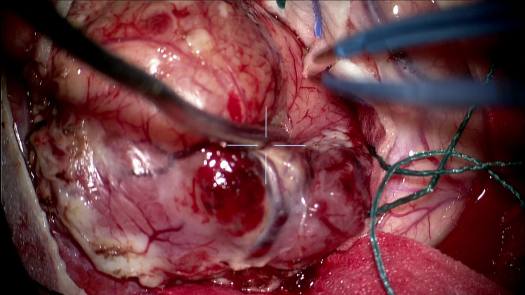

Resezione microchirurgica di tumore cerebrale (glioma alto grado cortico-sottocorticale) frontale dx